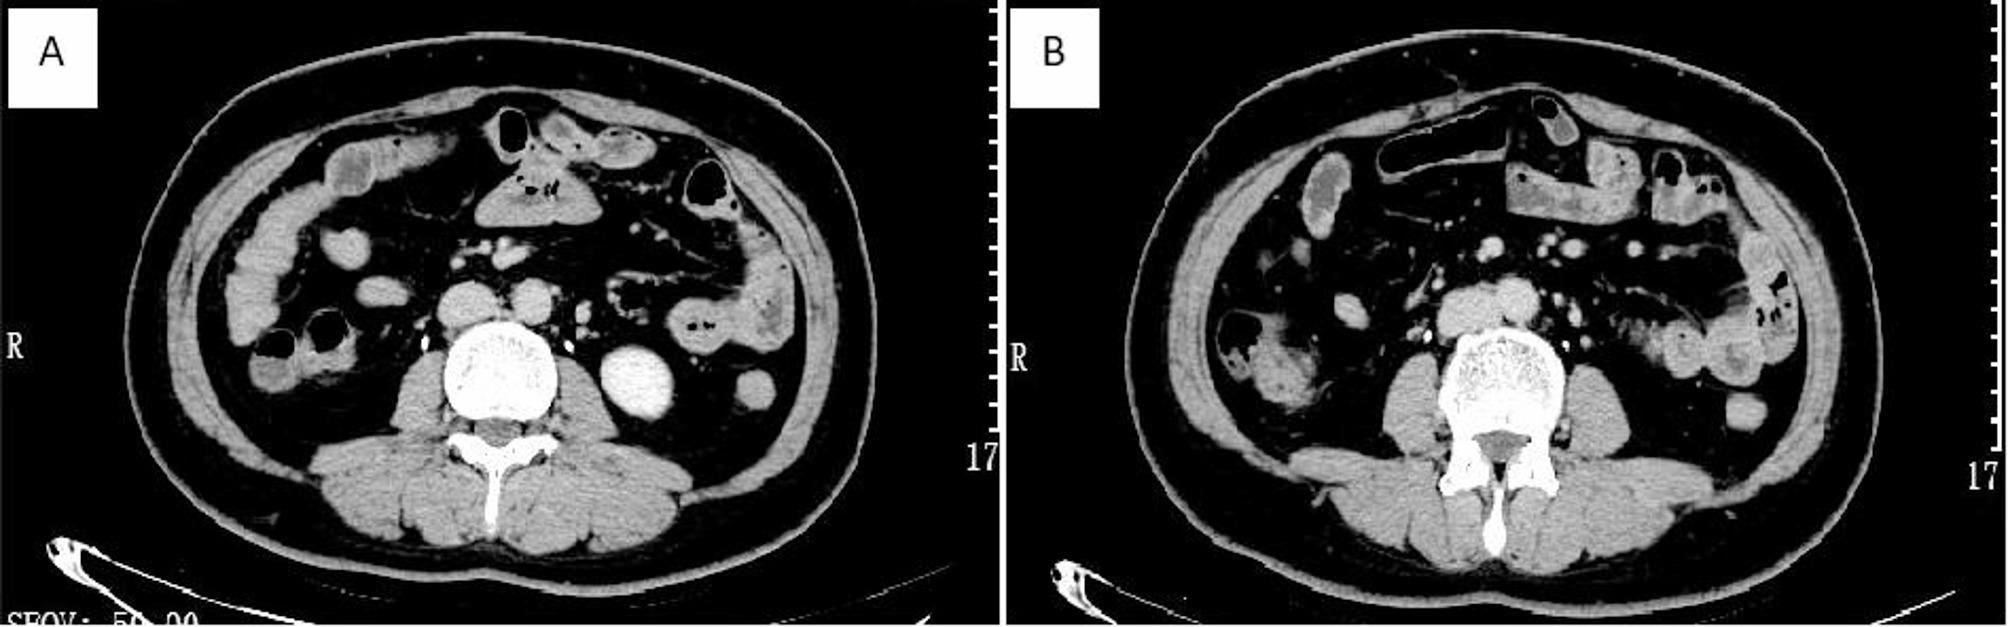

Abstract Image